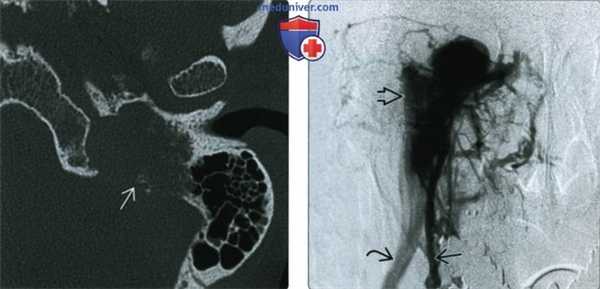

(Слева) При аксиальной КТ левой височной кости определяется дольчатое мягкотканное образование в нижних отделах мыса улитки, сопоставимое с ГТП.

(Справа) При КТ визуализируется крупное объемное образование в полости среднего уха. Опухоль приводит к выпячиванию барабанной перепонки кнаружи вокруг «пупка» (umbo) в области рукоятки молоточка. Обратите внимание на распространение в проксимальные отделы евстахиевой трубы и снижение пневматизации ячеек сосцевидного отростка из-за обструкции входа (адитус).

(Слева) При КТ левой височной кости в аксиальной проекции определяется параганглиома яремного гломуса; видны типичные инфильтративнодеструктивные изменения окружающей кости. Вероятно, больной предъявляет жалобы на пульсирующий шум в ухе, а за барабанной перепонкой визуализируется объемное образование красного цвета.

(Справа) При селективной ангиографии восходящей глоточной артерии в передне-задней проекции определяется интенсивное заполнение параганглиомы яремного гломуса контрастным агентом. Обратите внимание на раннее заполнение дренирующей вены через артериовенозные шунты. Часто для контроля кровопотери перед хирургическим вмешательством выполняется эндоваскулярная эмболизация.